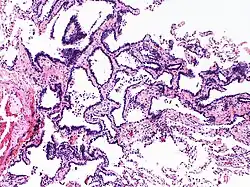

Hyperplasie adénomateuse atypique

L'hyperplasie adénomateuse atypique (HAA) est une lésion hyperplasique des pneumocytes bordant les alvéoles pulmonaires et présentant des anomalies cytonucléaires discrètes[1]. Ce terme est préconisé par l'Organisation mondiale de la santé dans sa classification des tumeurs de 2011, puis maintenu et précisé dans les versions de 2015 et 2021. Il caractérise une lésion glandulaire précurseur (précédemment dite lésion préinvasive) de très petite taille[2],[3].

Cette anomalie, de petite taille, inférieure ou égale à 5 mm[3], est une dysplasie, précancéreuse, précurseur de l'adénocarcinome pulmonaire in situ[4]. Le terme de carcinome bronchioloalvéolaire, autrefois employé pour décrire cette lésion est désormais abandonné[4].